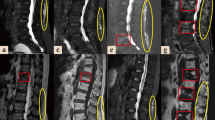

Pre- and postoperative images from two representative cases are shown in Fig. 1. Case 1 was a 74-year-old female (Hoehn & Yahr stage III) who presented with severe low back pain and a cauda equina sign (motor paralysis in both lower extremities) due to rapidly progressing L3 collapse within 3 weeks after injury. Vertebroplasty and PS fixation were performed, but PS loosening in upper segments occurred at 3 weeks after surgery with exacerbation of dyskinesia. The patient was able to maintain daily activities with only mild low back pain at 5 years after surgery, although decreasing lumbar kyphosis was observed after PS removal. Case 2 was a 70-year-old female (Hoehn & Yahr stage II) who presented with severe low back pain and a cauda equina sign (motor paralysis in both lower extremities) due to progressive L4 collapse. Anterior reconstruction and PS fixation were performed, and the patient has been asymptomatic for 3 years after surgery without instrumentation failure.

Case 1: A 74-year-old female (Hoehn & Yahr stage III) with severe low back pain and motor dysfunction due to rapidly progressive L3 osteoporotic collapse. Preoperative CT and T2-weighted MRI showed L3 collapse with canal stenosis by bony fragments that had retropulsed into the spinal canal. Instrumentation failure occurred early in the postoperative period with exacerbation of dyskinesia, and required removal of the pedicle screw, but daily activities were maintained despite a decrease in lumbar kyphosis at 5 years after surgery. Case 2: A 70-year-old female (Hoehn & Yahr stage II) with severe low back pain and motor dysfunction due to progressive L4 collapse. Preoperative CT and T2-weighted MRI showed L4 collapse with canal stenosis by bony fragments that had retropulsed into the spinal canal. The patient has been asymptomatic for 3 years after anterior reconstruction and pedicle screw fixation.

In surgery for type 2 or 3 low lumbar OVC in non-PD cases, short fusion from a posterior approach is ideal due to easier decompression for the lumbar canal and intervertebral foramen stenosis for fractured vertebra2. In PD cases, the surgical procedure is chosen based on severity of PD, type of OVC, neurological signs, endplate destruction, and kyphotic changes in the lumbar spine. For most patients with PD, additional reconstruction of the anterior column should be considered, especially for type 4 OVC. Anterior reconstruction using an expandable cage from a lateral lumbar approach and 1-above 1-below fixation as shown in case 2 in Fig. 1 might be ideal. In type 2 OVC in PD cases, VP + PS may be more likely to cause instrumentation failure and/or flesh compression fracture as shown case 1 in Fig. 1 than in non-PD cases, due to progression of postural abnormalities and decreased lumbar lordosis in the natural course of PD, which may lead to upper adjacent segment disease and degenerative spondylolisthesis. Because of rare PD cases with sclerotic changes such as in type 3 OVC, PS + PLF or PLIF are often not indicated. For a few patients with radicular pain or a high risk of instrumentation failure, there may be an option to wait for bone union with aggressive control of PD, and then perform laminectomy. These surgical strategies for low lumbar OVC in PD cases have been inferred from the pathological conditions observed in the present study and require verification in a future study.